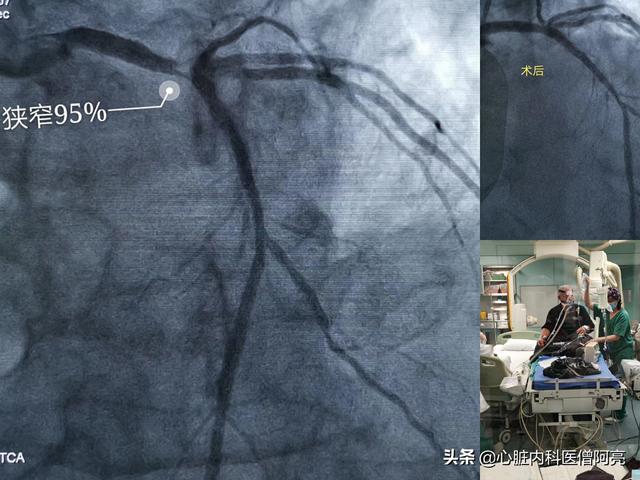

急性心筋梗塞で左主幹部が95%狭窄した80歳の患者に対する崔医師の緊急手術は、突然死の危険性が非常に高い中、慎重に完了した!

ステント業界や手術手技の進歩にもかかわらず、ステントの再狭窄率は依然として約5%である(以前は約20%であった)。このような患者は再狭窄のリスクが高いため、術後6〜9ヵ月後または1年後にフォローアップの画像診断を受けるように外科医から指示されることが多い。その主な目的は、1.ステントの状況を明らかにすること、ステント内増殖や再狭窄があるかどうか、2.未治療のまま残っている重症病変がさらに増悪を示すかどうか、増悪がある場合はそれに間に合うように対処し、まだ生命を脅かすほどではない心筋梗塞を回避すること、である!